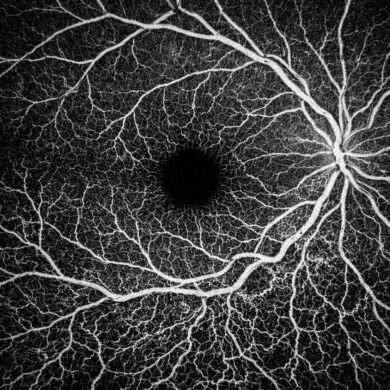

「血管が見える技術」として一気に広まったOCT-Aですが、実は“どこの血管を見ているか”は装置によって異なるのをご存知ですか?

OCT-Aが描出する代表的な「血管層」

OCT-Aは一般的に、網膜の表面(ILM)〜脈絡膜の浅層までを確認することができます。

| SCP(表層毛細血管層) | ILM〜視神経繊維層(RNFL内) | 緑内障、黄斑浮腫の血流変化。 |

| DCP(深層毛細血管層) | 内網状層〜内顆粒層 | 糖尿病網膜症、網膜静脈閉塞など。 |

| Outer retina | 外顆粒層〜視細胞層 | 通常は血管なし→CNVの検出。 |

| Choriocapillaris(脈絡膜浅層) | RPE直下〜脈絡膜毛細血管 | AMD、PCV、脈絡膜新生血管など。 |